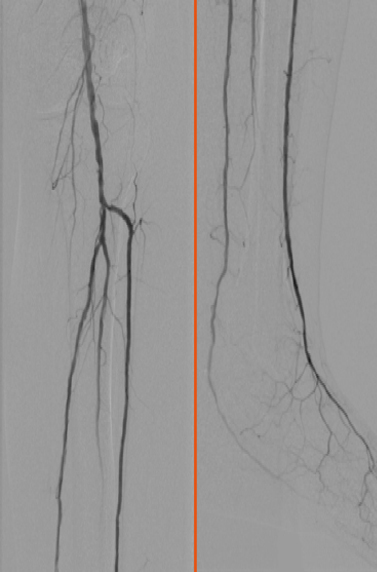

Vorher

1-Gefäßversorgung der Arteria fibularis.

Nachher

3-Gefäßversorgung im Unterschenkel.